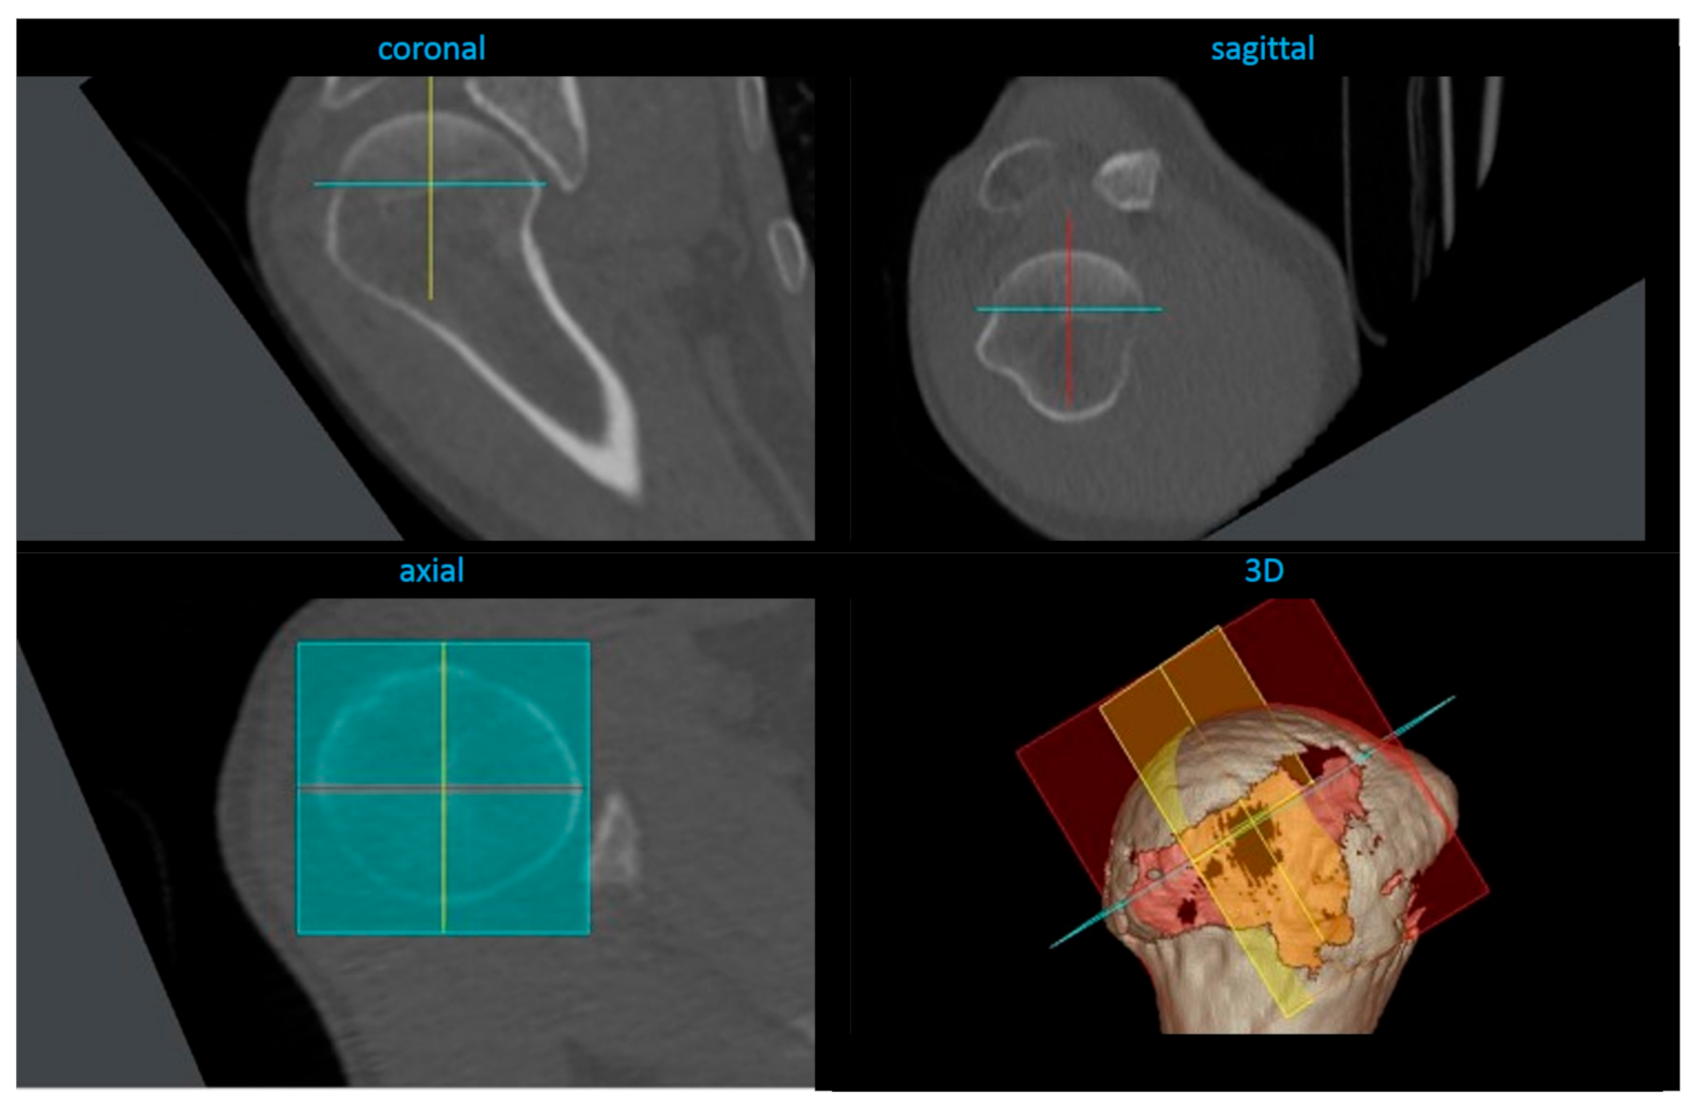

2.4. Radiological Analysis